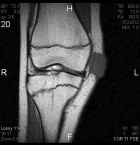

14 year old female with a tender right knee mass which has been enlarging for five months